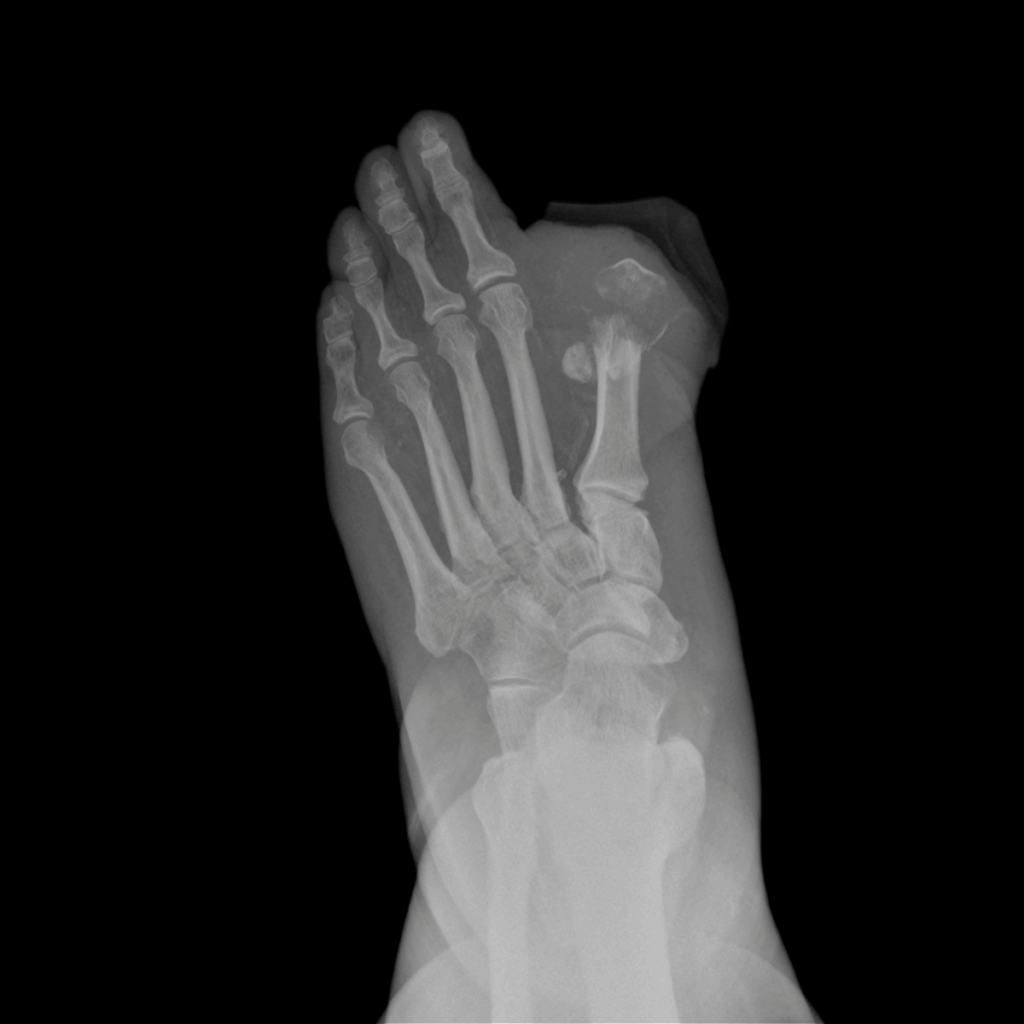

Osteomyelitis Overview

Osteomyelitis is an infection of the bone, usually caused by bacteria. It can affect any bone in the body but commonly involves the long bones of children and adults, spine, and pelvis. If untreated, it can lead to bone destruction, chronic infection, and impaired function.